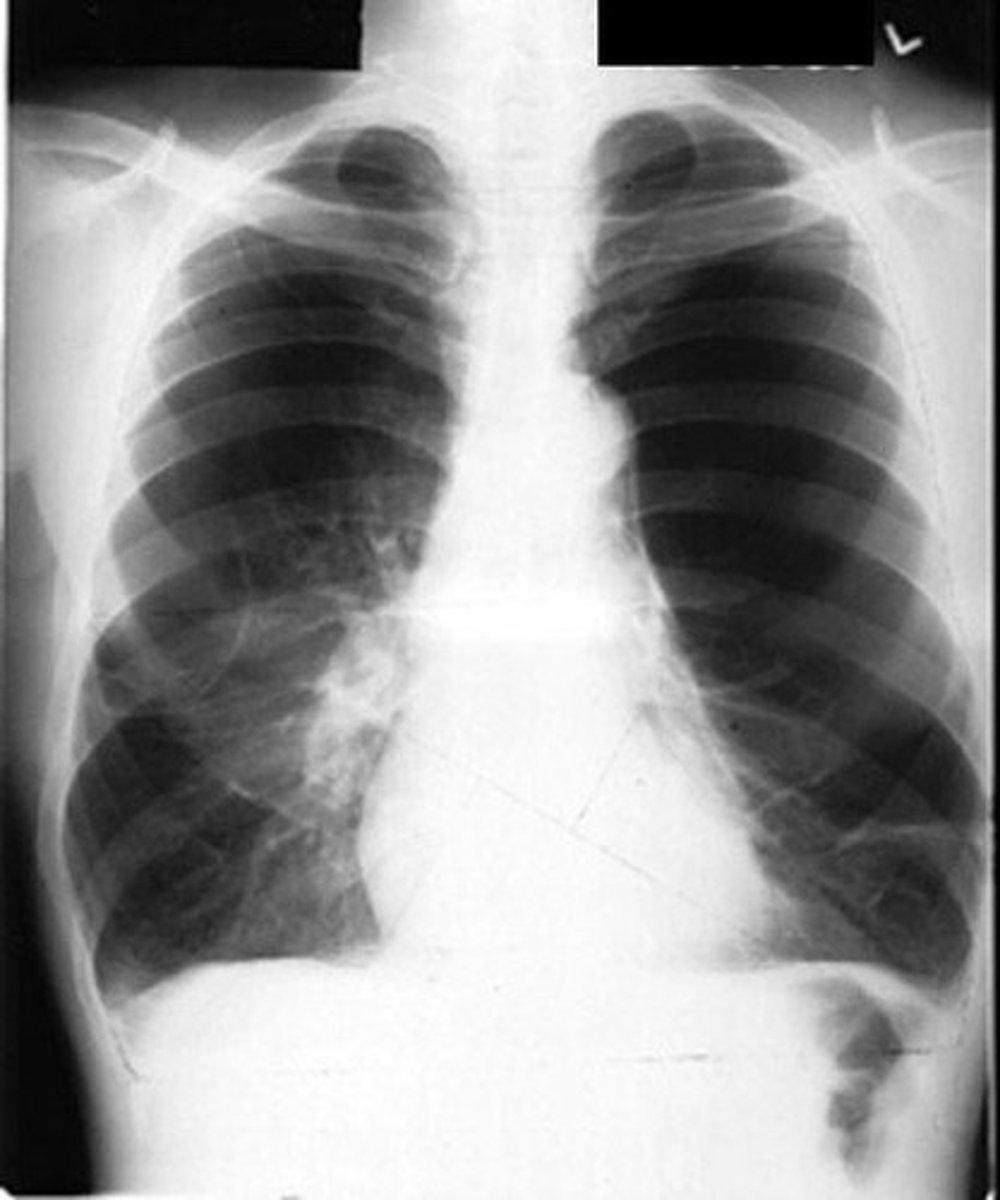

Chest x-ray

Imaging to rule out other lung diseases.